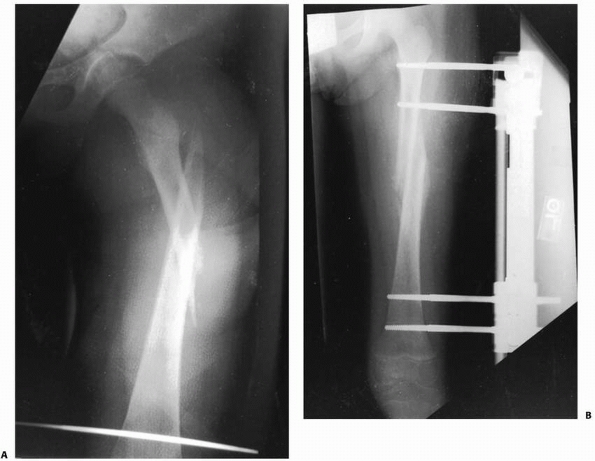

![]() |

FIGURE 22-20 AP (A) and lateral (B)

x-rays a low-energy short oblique fracture through a fibrous cortical defect in the distal femur; this type of fracture is not unusual. The surgeon judged that there was enough distance between the fracture site and the growth plate to allow external fixation. AP (C) and lateral (D) x-rays 3 weeks after external fixation shows early callus and good alignment. The external fixation was removed shortly after this x-ray and the child was placed in a long leg cast, with weight bearing as tolerated. |